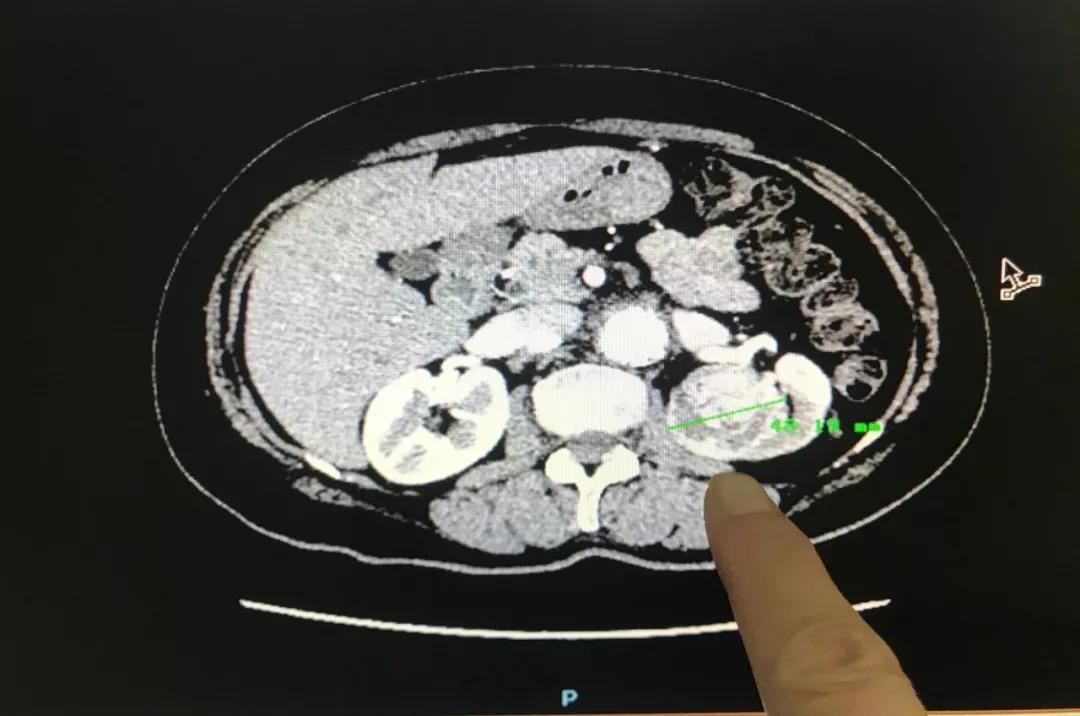

林(lín)英立博士接診後詳細詢問(wèn)了(le)王阿姨之前的(de)病史,随即安排了(le)相(xiàng)關檢查。“從(cóng)B超檢查結果可(kě)ε以發現(xiàn)腎占位腫瘤已經增長(cháng)至4.8公分(fēn),比原來(lái)增大(dà)了(le)很(hěn)多(duō),這(zhè)并不(bù)是(shì)一♠個(gè)好(hǎo)的(de)征兆。”